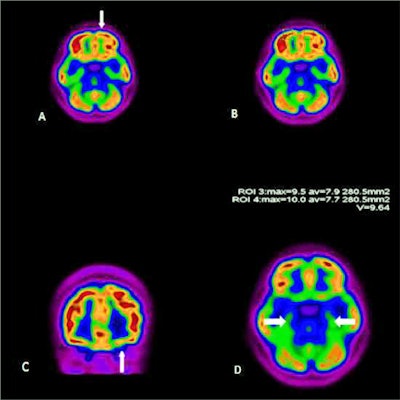

COVID-19 pneumonia is FDG-avid and numerous studies documented lung uptake in both asymptomatic and symptomatic patients.

One of the earliest case reports of PET/CT imaging of COVID-19 described four presumed cases with pulmonary involvement. The study found at least two lobes showed SUVmax values ranging from 4.6 to 12.2 in areas that indicated ground-glass opacities on initial CT. In three of the four cases, FDG-positive supraclavicular and mediastinal nodes were seen with SUVmax ranging between 5.4 and 7.